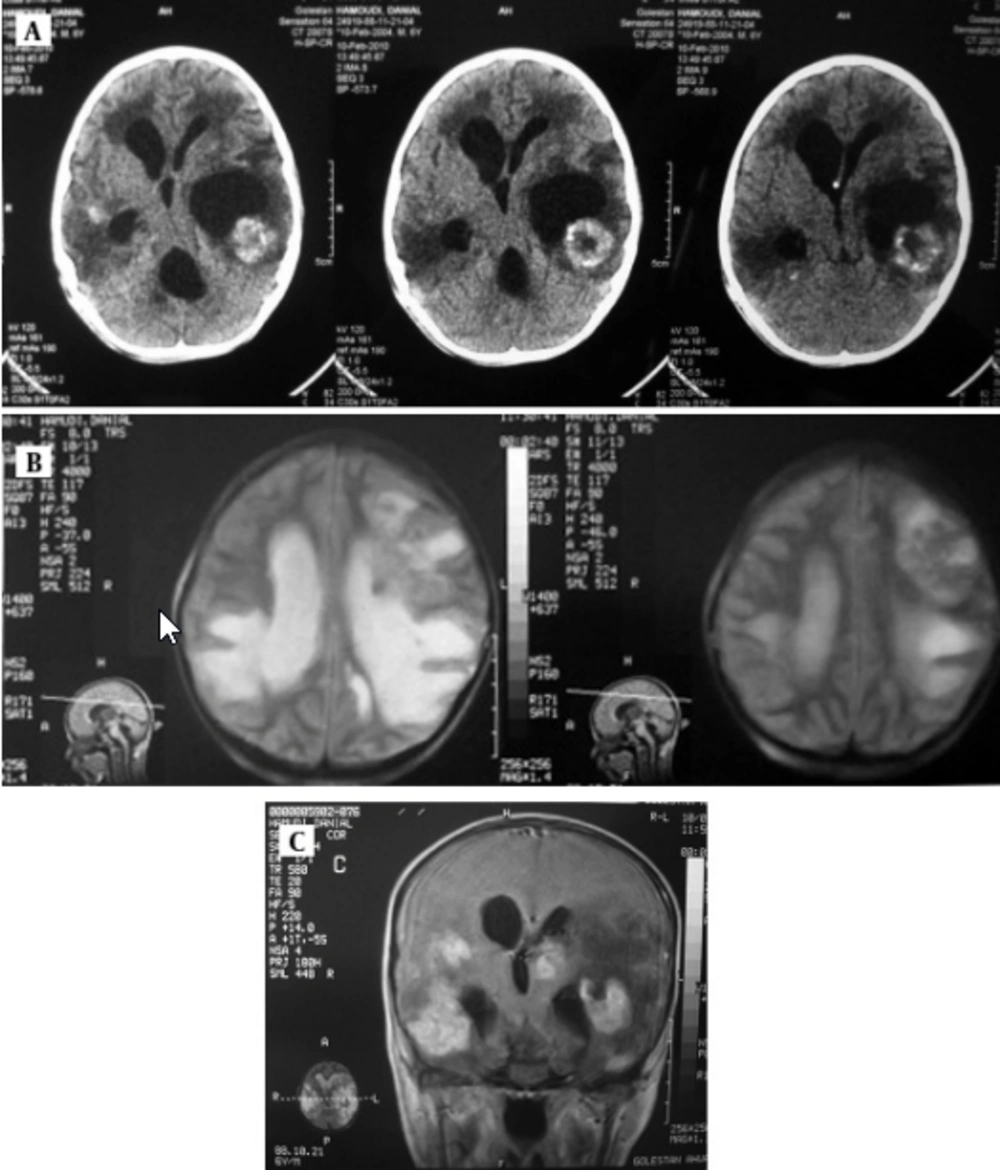

Case 2: A six-year-old boy with acute myeloblastic leukemia (AML) diagnosed in 2010 and was on maintenance treatment. Two months ago he was admitted to a hospital because of fever. Administration of antibacterial, antifungal and antiviral medicine did not control the temperature and due to generalized status tonic clonic convulsion, patient transferred into the intensive care unit (ICU).

Serological examination for anti- Toxoplasma antibody (Ig M) rate by Chemiluminesans (Roche kit) was more than 9 and Ig G was 6 IU/mL. Brain MRI revealed marked communicating hydrocephaly with corticomedullary junction of both temporal. Hyperdense lesions on T1 with surrounding vasogenic edema and intermediate signal on T2 with bright signal vasogenic edema and on post contrast images multiple enhancing lesions were seen (Figure 3). The patient received pyrimethamin, sulfadiazine and leucovorin. The patient is alive and has neurogic sequel.